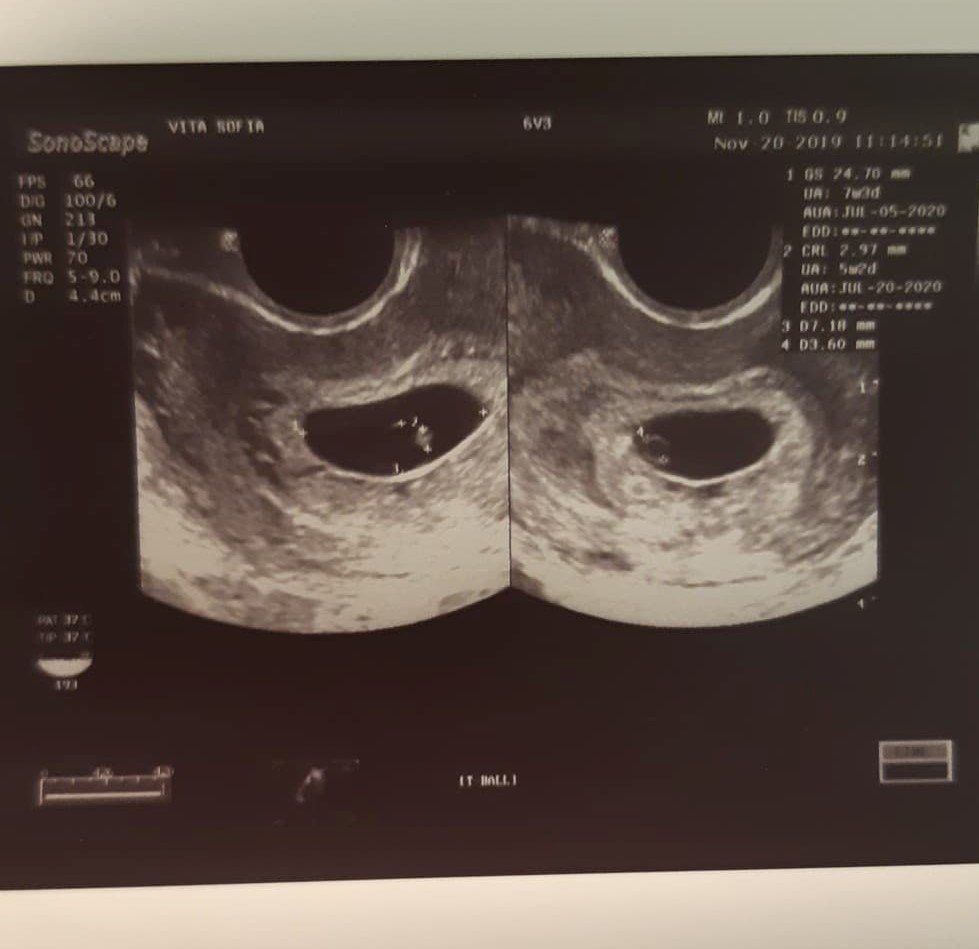

Аз днес имах много странен преглед, сякаш докторката не беше същата жена, при която ходих последните няколко пъти. Видя на ехографа още едно жълтъчно мехурче, по-малко от другото (???), не видя сърдечни пулсации (а в петък, на 15ти, в Шейново видяха), попита ме матката ми винаги ли е била така обърната и аз онемях, защото цял живот ми повтарят колко перфектни органи имам като по учебник и сега изведнъж - обърната матка???

Ембриончето според нея отговаря на 5 седмица и 2 дни, а в Шейново в петък го измериха 6 седмица и 1 ден. Отново отговорът е, че заради удължения цикъл и неясно кога настъпилата овулация не може да се каже конкретно и да се измери и дали е нормално да няма сърдечни пулсации.

Отделно, за зацапването ми не се предприе и говори каквото и да е, според нея не е опасно, каза че плодния сак бил чудесно прикрепен. Не ми обясни какво е това второ жълтъчно мехурче, само каза че я озадачава.

Ще ви приложа снимки от ехографа и от болничния лист, за да прочетете и ако можете да хвърлите някаква яснота, че вече съвсем се шашнах.

Ето и снимките на изследванията, ако можете да ги видите и да кажете какво мислите, ще съм много благодарна: